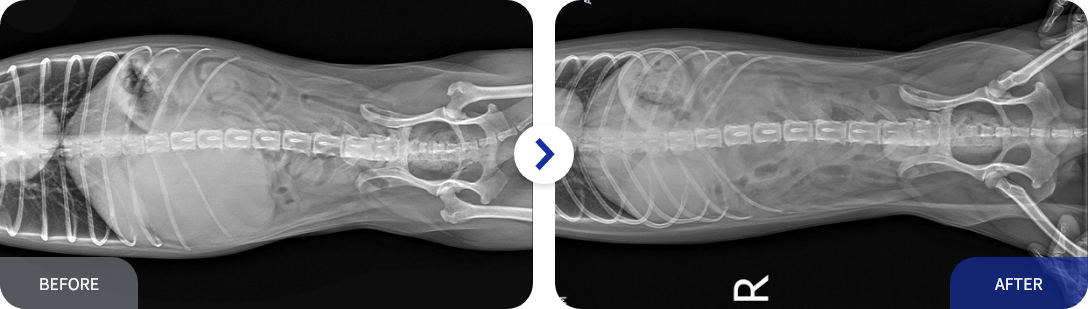

종양 수술 사례

• 신장종양 수술 전, 후